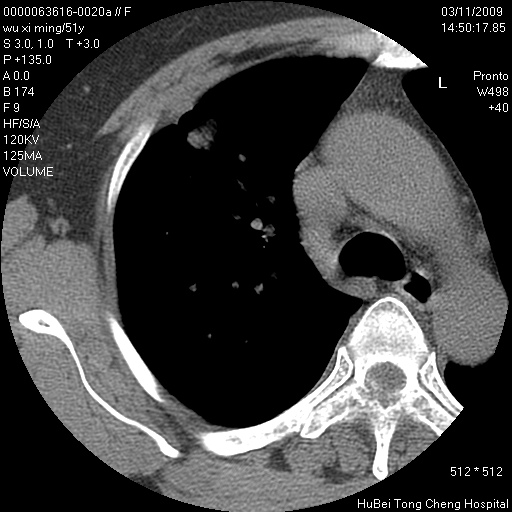

患者 女,51岁。因“胆囊炎,胆囊结石”,行常规术前胸部x线检查发现:右上肺结节病灶,建议行进一步检查。患者无咳嗽、咳痰及咯血等呼吸道症状,近期出现背部疼痛不适。

胸部ct轴位平扫(层厚10mm,螺距1.5,重建间隔10mm;部分层面:层厚3mm,螺距1.0,重建间隔3mm),图像如下:

右肺周围型肺癌伴肺内转移信胸椎转移

支持--右肺周围型肺癌---胸椎转移

右肺周围型肺癌伴肺内转移及胸椎转移。已无手术机会。